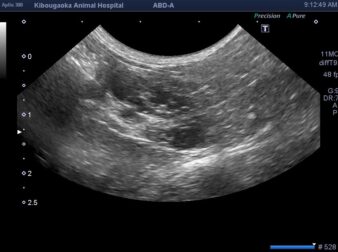

卵胞嚢腫

生殖器